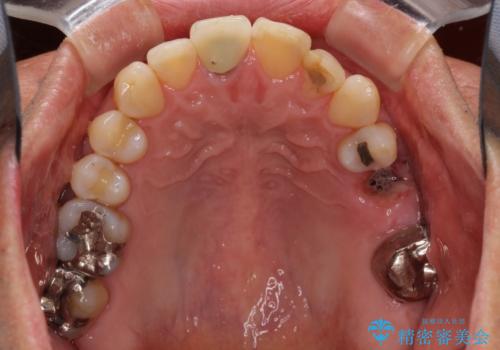

- 奥歯を他院で抜歯した後、インプラント治療を希望とのことで来院された患者様です。

ブリッジの支台を抜歯したことで2本のインプラントが必要であり、その後方はインプラント埋入に必要な骨量が不足していたため、上顎洞粘膜の挙上を行うこととしました。

また、残っている最後方歯は手前に倒れてきていたため、部分矯正により奥に移動させてから、インプラント埋入を行うこととしました。